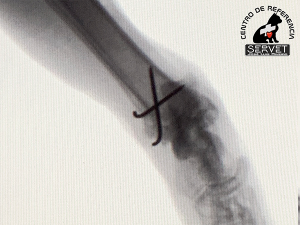

En nuestro caso, varias pequeñas agujas colocadas en el lugar adecuado logran que las fracturas se mantengan estables con abordajes quirúrgicos mínimos.

Preservar la integridad de ligamentos, tendones y músculos es el objetivo de la cirugía de mínima invasión. No nos olvidemos que los tejidos blandos también son necesarios para caminar.